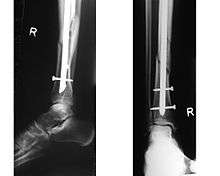

An intramedullary rod, also known as an intramedullary nail (IM nail) or inter-locking nail or Küntscher nail (without proximal or distal fixation), is a metal rod forced into the medullary cavity of a bone. IM nails have long been used to treat fractures of long bones of the body. Gerhard Küntscher is credited with the first use of this device in 1939,[1][2] during World War II, for soldiers with fractures of the femur. Prior to that, treatment of such fractures was limited to traction or plaster, both of which required long periods of inactivity. IM nails resulted in earlier return to activity for the soldiers, sometimes even within a span of a few weeks, since they share the load with the bone, rather than entirely supporting the bone.[3]

Although stainless steel was used for older IM nails, titanium has several advantages, including lower mechanical failure rates and improved biocompatibility.[4] However the biggest problem with the earlier designs was the failure to prevent collapse or rotation in inherently unstable fractures. This was addressed by the introduction of the concept of 'locking' of the nails using bolts on each end of the nail (thus fixing the nail to the bony cortex and preventing rotation among the fragments), leading to emergence of locked IM nailing, which is the standard today.[3]